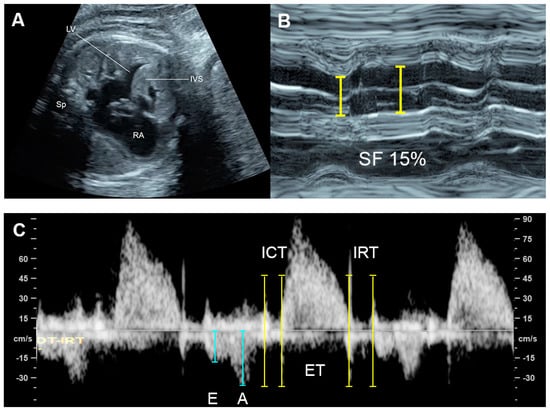

| Shortening fraction | Decreased (<28%) | Systolic dysfunction |

| Tei index | Increased > 0.50 | Global cardiac dysfunction |

| ICT: 28 (22–33) ms | Prolonged | Systolic dysfunction |

| IRT: 34 (26-41) ms | Prolonged | Diastolic dysfunction |